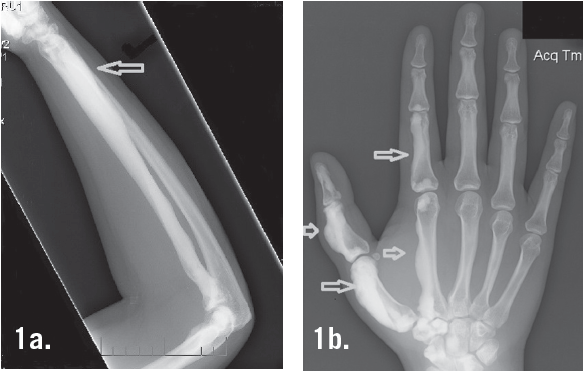

Syeda M. Sayeed, MD

A 23-year-old female presented with painful, slow-growing masses on the left thumb and forearm for 5 years. The medical history revealed no trauma and no sports-related injury.